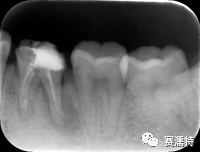

祝自洋老師案例